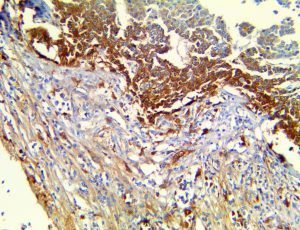

It is the ICU physician who is most likely to witness one of the deadliest manifestations of the abnormal immunological response, the cytokine storm syndrome (CSS). This response is also referred to by some as the cytokine release syndrome (CRS). CSS is characterized by continuous activation and expansion of macrophage and lymphocyte populations, which secrete large amounts of cytokines, causing the cytokine storm. This massive cytokine release is akin to hemophagocytic lymphohistiocytosis (HLH) disease, a syndrome characterized by initial unchecked and persistent activation of cytotoxic T lymphocytes and NK cells.

Clinical and laboratory manifestations of HLH include fever, enlarged liver and/or spleen, neurologic dysfunction, coagulopathy, liver dysfunction, cytopenias (i.e., low levels of erythrocytes, leukocytes, and/or platelets), hypertriglyceridemia, hyperferritinemia, hemophagocytosis, and eventually diminished NK cell activity as the immune system becomes progressively paralyzed. HLH can be familial (primary HLH) or secondary to another disease process (sHLH), such as rheumatic disease, in which it is referred to as macrophage activation syndrome (MAS, characterized by elevated ferritin).

This activation induces inflammatory monocytes to highly express IL-6, starting a localized and then systemic cascade effect that results in hyperproduction of IL-6, which accelerates the inflammatory process. Because IL-6 also increases vascular permeability, excessive levels cause blood vessels to become very leaky. This, along with clotting factors released from vascular endothelial cells, stimulates the coagulation cascade, resulting in microthrombosis (tiny clots), which leads to ischemia and tissue death of the kidney, intestines, heart, liver, brain and extremities.